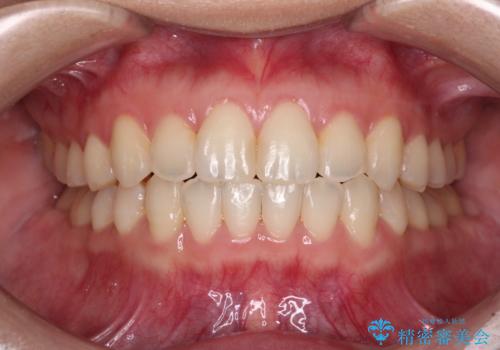

歯列全体のクロスバイトを治したい ワイヤー装置による矯正治療

- 上下のデコボコと前歯のクロスバイトを改善したいとのことで来院された患者様です。

マウスピース矯正での自己管理には自信がないとのことで、ワイヤー装置による矯正治療を行うこととしました。

デコボコの程度は強かったのですが、口元の突出感はなかったため、非抜歯矯正としました。